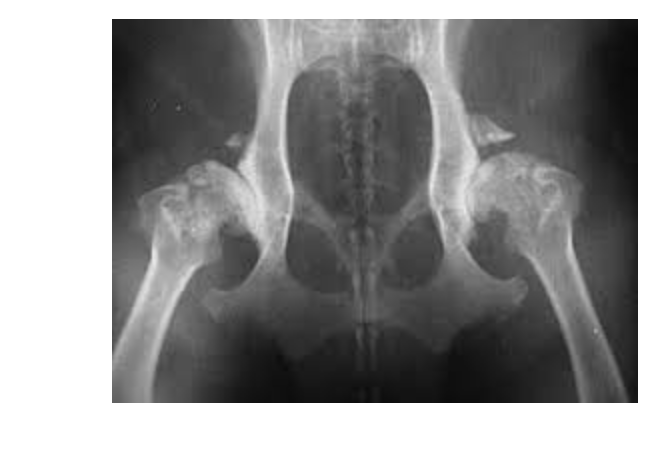

HD what does it look like of radiographs

Flattened femoral head

Thickened femoral neck

Shallow/ sclerotic acetabulum

Numerous osteophytes

What are some signs of arthritic changes

Acetabulum is almost not visible

Bone spurs above hip joints

Thickening and remodeling of the femoral head